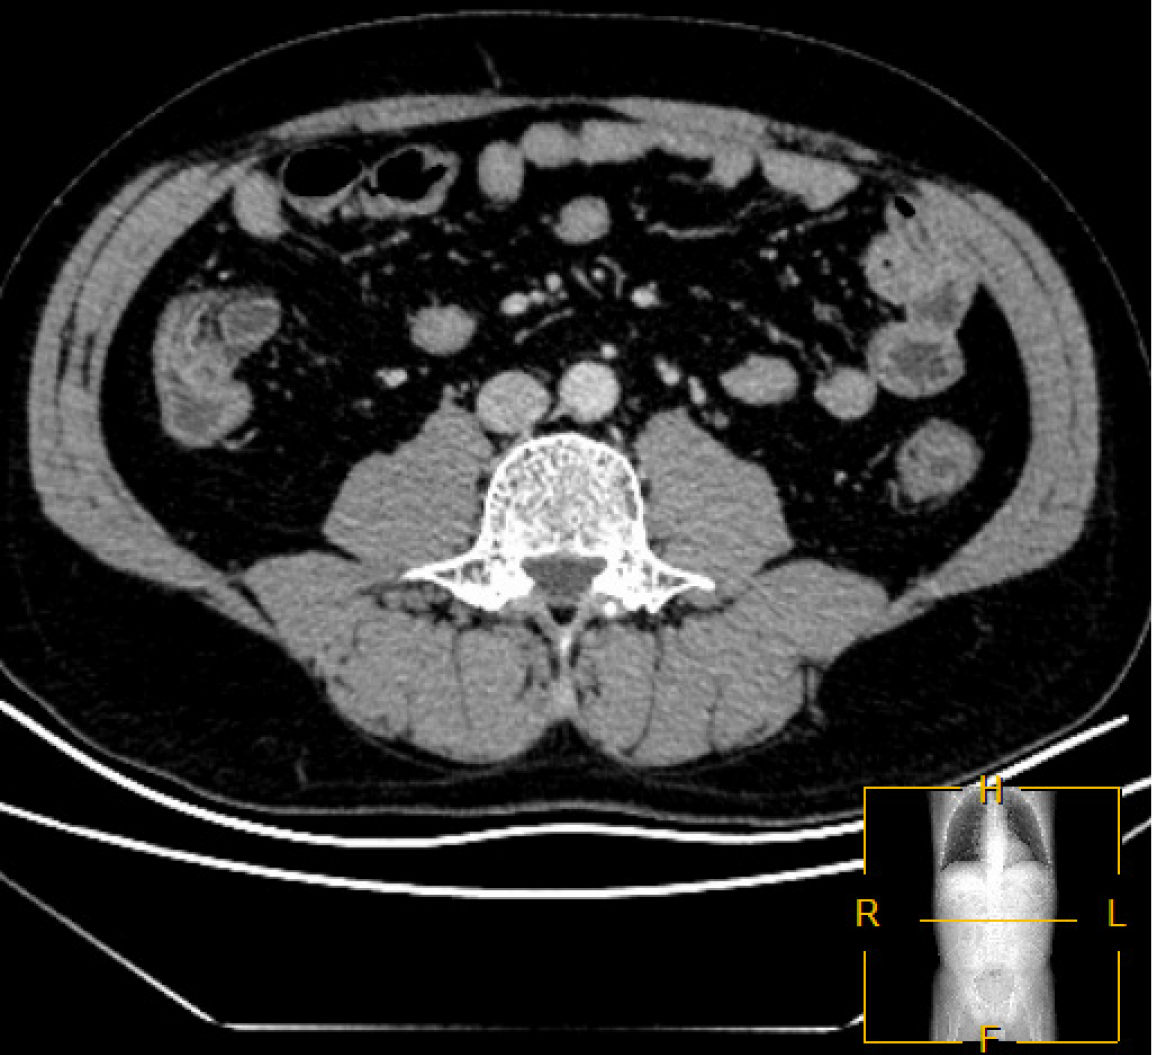

OUTCOME AND FOLLOW-UP

The patient’s bowel condition improved 1 month after the first FMT; the frequency of evacuation was 1-2 times a day, the stools were yellow, molded, and soft (Bristol 4 and 5), and there was an occasional feeling of incomplete evacuation. Although a few ulcers and tissue hyperplasia were still present in the patient’s oral cavity, the patient gained approximately 10 kg over the previous month. The patient underwent a second and third FMT (in September 2021 and March 2022, respectively) to maintain the therapeutic effect and was treated with thalidomide to regulate immunotherapy. A follow-up colonoscopy 9 months after the third FMT (Figure 5) demonstrated improved endoscopic findings compared to the previous procedure. In January 2024, the stool frequency was 2-3 times per day after an out-of-town business trip, with a thinner stool consistency (Bristol 6 predominantly) compared to the previous one. Concurrently, the patient developed progressive numbness in both lower extremities, whereas the oral ulcers showed gradual improvement and ultimately resolved. Following multidisciplinary consultation, the bilateral lower limb numbness was considered an adverse effect attributable to thalidomide, with a cumulative exposure of 28.75 g. Accordingly, thalidomide therapy was discontinued, and a fourth FMT was subsequently administered. The therapeutic effect was further consolidated by treating the patient with a fifth FMT in July 2024 (Figure 6). The pathological findings from the colonoscopic biopsy during the fifth FMT session demonstrated marked improvement in the lesion compared to previous assessments. This manifested as moderate-to-mild lymphocytic infiltration with mild atypia observed in the lamina propria (descending colon) and the muscularis mucosae. Concurrently, a repeat abdominal CT (Figure 7) scan revealed no enlarged lymph nodes in the ascending colon, sigmoid colon, or mesentery. At present, the patient’s diarrhea has significantly improved; his evacuation frequency is 1-2 times a day, his stools are yellow, molded, and soft (Bristol 4 and 5; with no black stools or fresh blood stools), and he shows no mouth ulcers (Figure 1B). The patient has gained significant weight since the start of FMT (Figure 8), from 60.9 kg to 85 kg, and his BMI has increased from 19.01 to 26.53. The patient also expressed a high degree of satisfaction with the treatment outcome. Clinically significant improvements were observed in both functional status and psychological well-being. The resolution of diarrheal symptoms has restored his ability to maintain a normal occupational and social routine, without disruptions to professional commitments or daily activities. Furthermore, the patient reported markedly improved mood and a positive outlook regarding future health prospects. No FMT-related adverse events have been observed since the initial FMT. As of the submission of this report, the patient continues to undergo monitoring and one intestinal bacterial transplant per year.

Figure 7

Figure 7 Post-fecal microbiota transplantation abdominal computed tomography scan revealed no evidence of lymph node enlargement in the ascending colon, sigmoid colon, or mesenteric region.